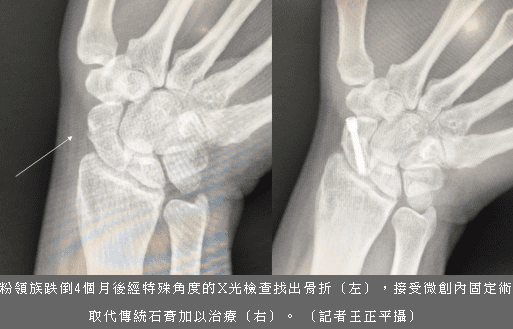

四個月前打比賽手舟骨骨折 最近才發現 有什麼治療的好方法嗎 每日頭條

跌倒手撐地痛4個月才知骨折 Tako